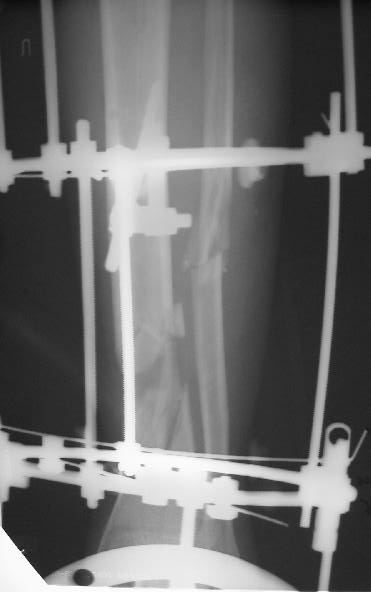

Больному 7 дней назад плита придавила голень стопу. Диагноз Открытый ( 3 б по Каплану) сложный многооскольчатый перелом с выраженным раздроблением н/3 диафиза голени, перелом лодыжек без смещения, перелом основания 5 плюсневой кости с небольшим смещением.

По моему мнению во-первых нужно гешить проблему мягких тканей, для этого провести вторичную и третичную и сколько понадобится обработок при этом удаляя все свободные и инфицированные костные фрагменты - безжалостно и после этого надежное закрытие кожного дефекта с запасом, лучше всего микрохирургический соседистый лоскут . Когда мягкие теани будут готовы в зависимости от размера дефекта можно решить что делать. Лично я предпочитаю замещение дефекта по Илизарову в классическом варианте - остеотомия проксимального отдела тибии и дистальное перемещением с формированием регенерата. Тем более аппарат уже есть. Я бы не стал фиксировать стопу. Судя по снимку дистальный фрагмент достаточно большой, но посмотрим что останется после последней ХО.

А где дефект? Толком не видно.

Согласен с коллегами , что фиксация стопы тут избыточна, и что дефекта не видно.

Учитывая, что травма получена в результате придваливания голени плитой, можно расчитывать на проблемы с заживлением мягких тканей. Поэтому, на мой взгляд, конечно удобнее вести больного в аппарате Илизарова. После полного заживления мягких тканей, при необходимости (дефект, действительно, на данных снимках можно только заподозрить), произвести кортикотомию и постепенно закрыть дефект большеберцовой кости. Можно закрыть дефект путем перемещения фрагмента малоберцовой кости на сосудистой ножке, но технически, для меня это сложнее. По поводу комплектации аппарата - я считаю, что лучше зафиксировать стопу, для того, чтобы исключить микроподвижность в области перелома, поскольку дистальный фрагмент достаточно короткий. Лучше перебдеть, чем недобдеть.

Больного прооперировал, обработку мягких тканей на голени не стал делать, думаю, некроз по краю швов на голени заживет под струпом (рис 3). На стопе удалил некротические ткани, готовлю ее к аутопластике (рис 2).

На дополнительных снимках итраоперационно видна значительная потеря массы (рис 6 рис 1). Хотя на снимках контрольных после операции вроде дефекта значительного нет. Все же придется, как-то замещать дефект костный на голени, думаю подготовить морально больного к повторной операции костной пластике, после заживления ран.